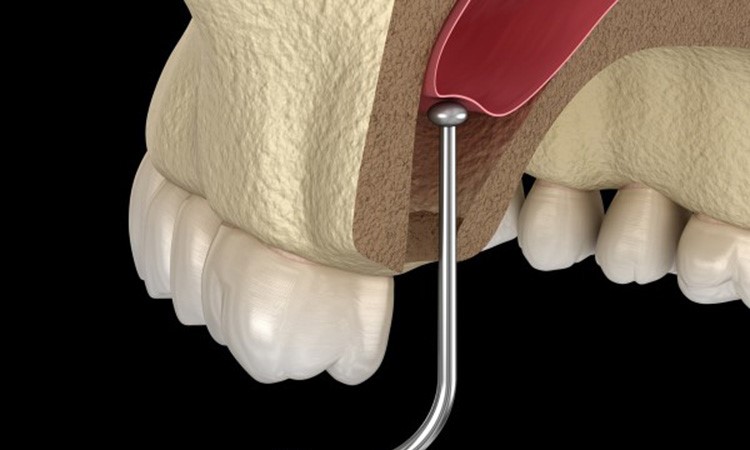

Nâng xoang hở là kỹ thuật nha khoa được thực hiện nhằm mục đích đẩy cao phần xoang lên trên, tránh va chạm với trụ Implant khi thực hiện cấy ghép. Kỹ thuật này còn được gọi là nâng xoang bằng cửa sổ bên, thực hiện cắt bỏ một phần xương hàm theo hình tròn.

Nha sĩ sẽ tiến hành rạch một đường để lộ ra xương hàm, sau đó cắt bỏ một phần xương này đi. Tại vị trí này, phần xương sẽ được nâng lên, sau đó lấp đầy bằng quá trình cấy ghép thêm xương. Nâng xoang giúp tăng kích thước của xoang hàm theo chiều ngang, tăng lên khoảng vài mm, tạo điều kiện thuận lợi khi cấy ghép trụ Implant.

Bước 4: Tách và nâng xoang

Nha sĩ tiến sử dụng kẹp chuyên dụng, nâng phần xương hàm lên, giữ cho màng xương ở nguyên vị trí này.